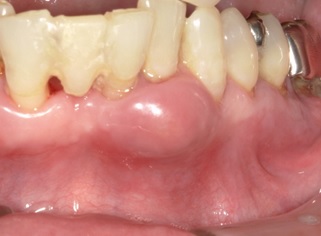

B:歯周病とは

「歯周ポケット」と呼ばれる、歯と歯ぐきのすき間にある溝から病気が始まります。

歯みがきが正しくできていないと、次第に歯周ポケットには細菌のひそむ汚れがたまっていき、歯ぐきの内部で炎症を起こします。